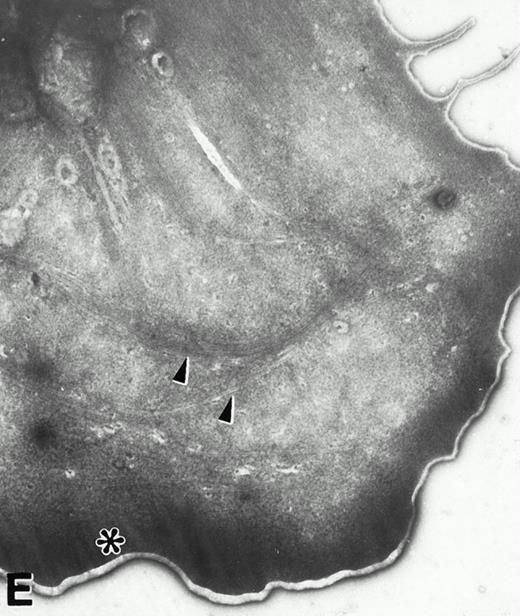

(A) Representative resting WF rat platelets prepared identically to resting Wistar platelets in Fig 2. (B through E) WF rat platelets allowed to adhere to Formvar-coated, carbon-stabilized grids from 30 seconds to 30 minutes, and subsequently fixed and stained with uranyl acetate. (B through E) illustrate the forms characteristic of WF rat platelet spreading, including platelets with stubby filopodia (B), lamellipodia (C), or fully spread forms (D and E). (E) shows the spread margin of a WF platelet at higher power. The arrowheads indicate microtubules and the asterisk shows the dense peripheral weave at the platelet margin. (B) 30-second adherent sample, (C) 1-minute adherent sample, (D and E) 30-minute adherent sample. (A through D, original magnification ×7,000; E, original magnification ×19,000).